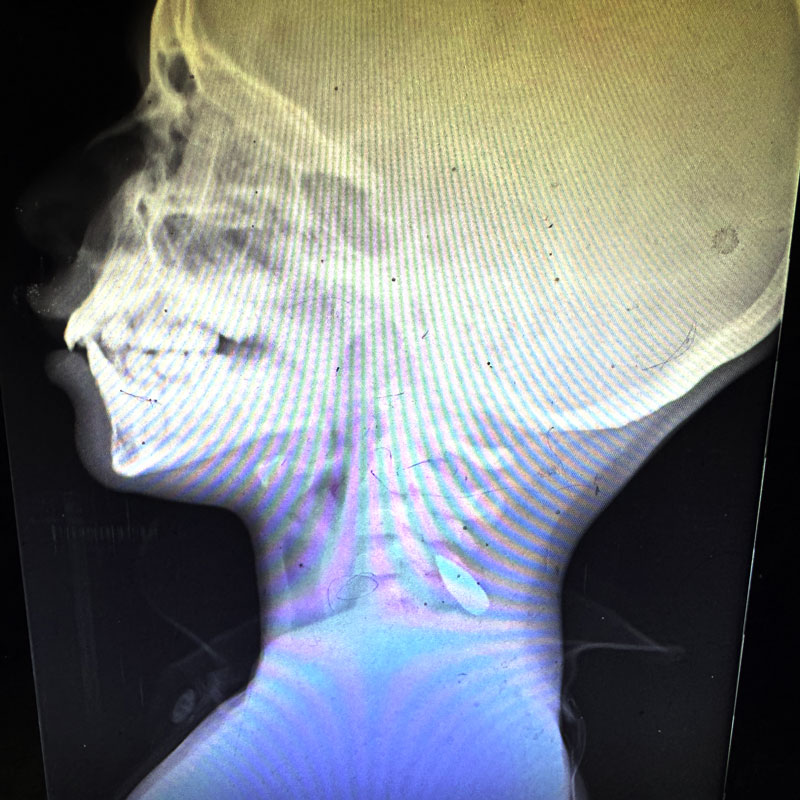

These photographs of X-rays were provided by Dr. Mimi Syed, who worked in Khan Younis from Aug. 8 to Sept. 5. She said: “I had multiple pediatric patients, mostly under the age of 12, who were shot in the head or the left side of the chest. Usually, these were single shots. The patients came in either dead or critical, and died shortly after arriving.” Dr. Mimi Syed

IB3.jpg

IB2.jpg

IB1.jpg